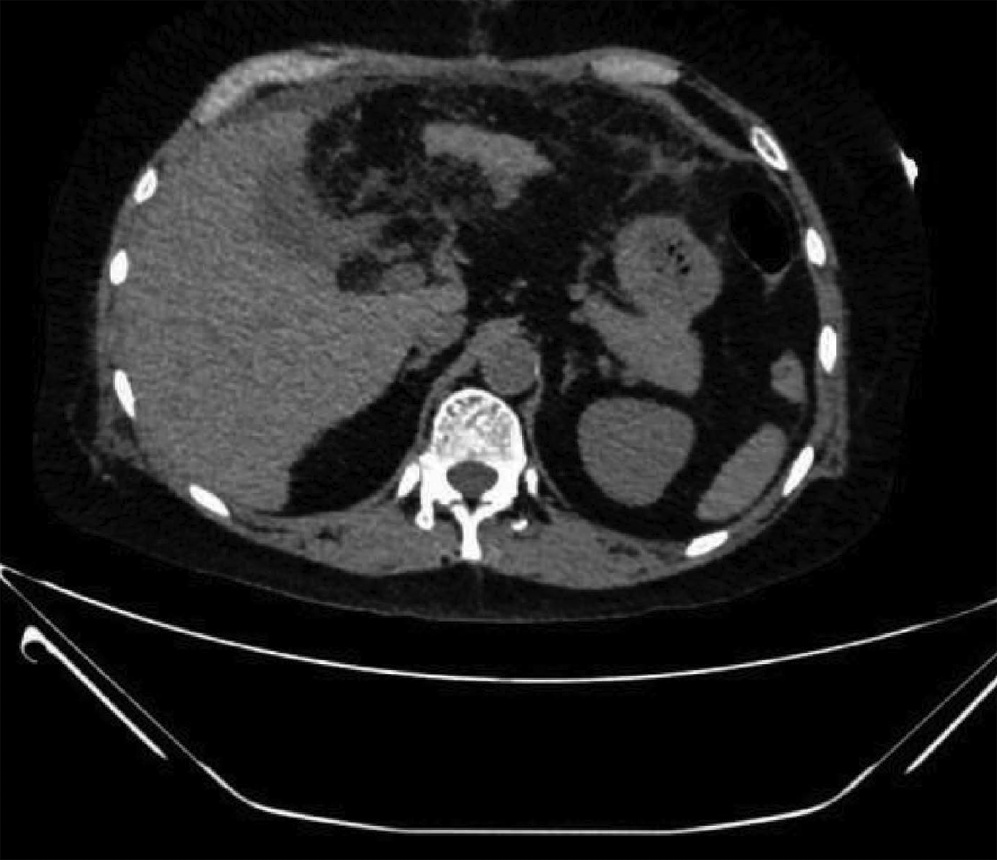

IgG4-related retroperitoneal fibrosis: A case report

Zhaoxia LI, Yang LIU, Nan LI, Zhuhui JI, Guijie XIN

2022, 38(5): 1126-1128. DOI: 10.3969/j.issn.1001-5256.2022.05.030

Abstract(758) HTML (364) PDF (2161KB)(55)

Abstract: